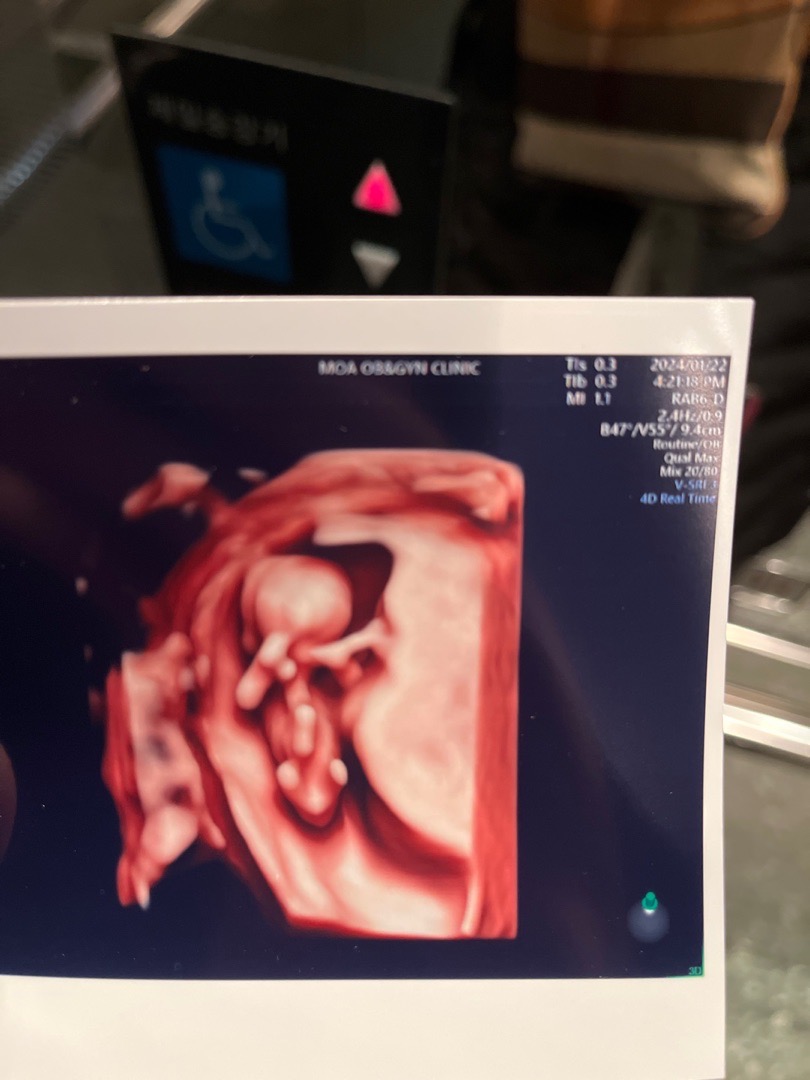

피까지 토해서 수액 맞으러와서 애기 초음파 봤어요

애기는 건강하고 양수도 많다고ㅠㅠ 그나마 위로가 되네요.. 11주 2일인데 언제 좋아질까요😭😭😭 그리고 혹시 사진 잘 보시는분들 애기 이거 혹 🌶️일까요..? 둘째는 딸 바라는데 허허,,,